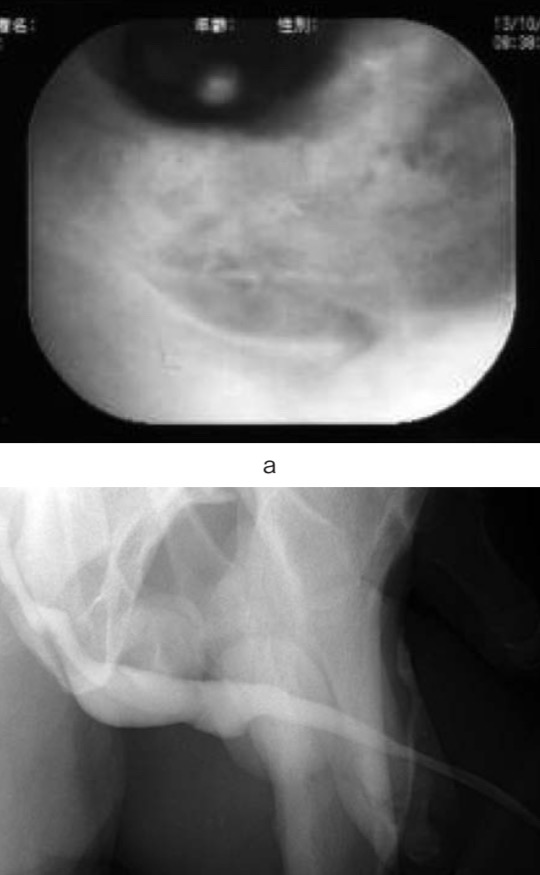

a : При уретроскопии свищ полностью зажил.

б: Цистоуретрография мочеиспускательного канала не показала утечки контрастного вещества из кожно-уретрального свища.